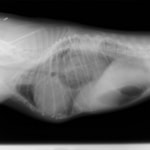

術前レントゲン

腹部臓器が胸腔内に脱出し、腹部と胸部の境界および心臓や肺の陰影が不明瞭になっています。また、胸腔内に消化管のガス陰影が認められます。

術後レントゲン

腹部臓器が腹腔内に戻り、腹部と胸部の境界および心臓や肺の陰影が明瞭に見えるようになりました。